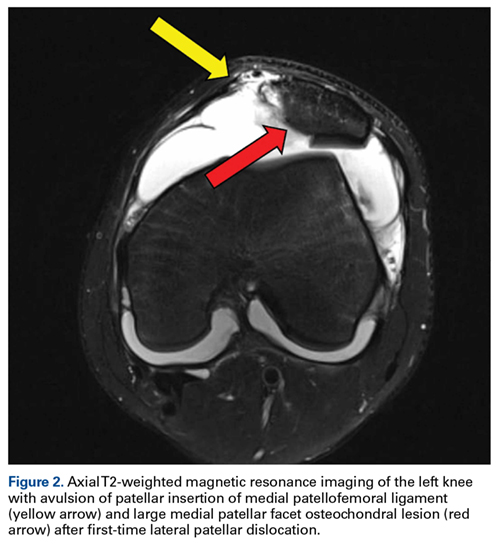

Although large osteochondral lesions may be visible on plain radiographs, MRI can be considered because of the relatively high incidence of osteochondral lesions in this population.21 In addition, MRI best determines the location and the extent of MPFL injury when early surgical intervention is being considered after discussion with the patient, or in cases of a concomitant osteochondral lesion.20 MPFL repair is best indicated in a young patient with a first-time patellar dislocation and a patella- or femoral-based bony avulsion or isolated patella- or femoral-based rupture (Figure 2). However, in a patient with a multifocal intrasubstance ligamentous injury, and in a high-level athlete being considered for surgery, MPFL reconstruction may provide more reliable outcomes.11,29Numerous open and arthroscopic MPFL repair techniques have been described.10,30-33 Nevertheless, comparative studies are limited, and the greatest debate about MPFL repair continues to be appropriate indications. Arthroscopic MPFL repair can be technically demanding and can fully visualize only patella-based injuries. In addition, all-arthroscopic repair techniques may place suture material in the joint, which causes concern regarding suture irritation. As a result, the majority of MPFL repair techniques described in the literature use an open approach, which typically includes a 4-cm to 5-cm longitudinal incision along the medial aspect of the patella. Sharp dissection is carried down through the medial retinaculum to the underlying joint capsule. The plane between the medial retinaculum and the underlying joint capsule is bluntly developed posteriorly until the medial epicondyle and the adductor tubercle are palpated. For a patella-based rupture, the MPFL is defined within layer 2, and 2 suture anchors are placed within the superior third of the patella. Although there are other patellar fixation methods, suture anchors provide adequate fixation with minimal risk of iatrogenic patellar fracture. With anchors in place, horizontal mattress sutures are placed in the stump of the MPFL. For femoral-based ruptures, the same surgical exposure is used to identify the MPFL. However, depending on the size of the incision and the mobility of the tissue, a second incision can be made posterior and parallel to the first—best achieved using a spinal needle to fluoroscopically localize Schöttle’s point.16 An incision is made in line with the spinal needle, and dissection is continued down to the previously developed extracapsular plane. Under fluoroscopic guidance (Figure 3), 1 or 2 suture anchors are placed at Schöttle point, and horizontal mattress sutures are placed through the avulsed MPFL femoral origin.